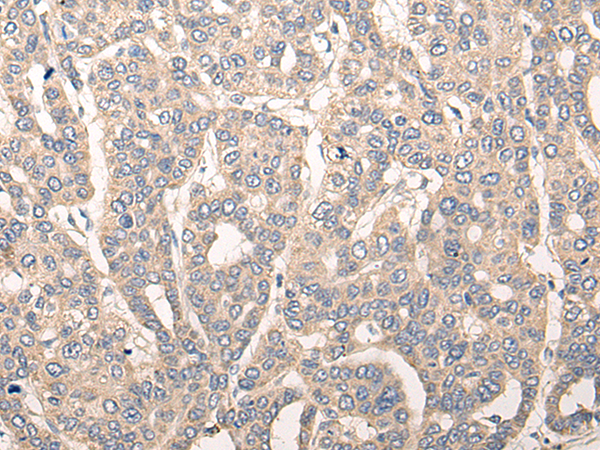

分类: 科研抗体货号: P09472别名:应用: IHC反应种属: Human, Mouse, Rat